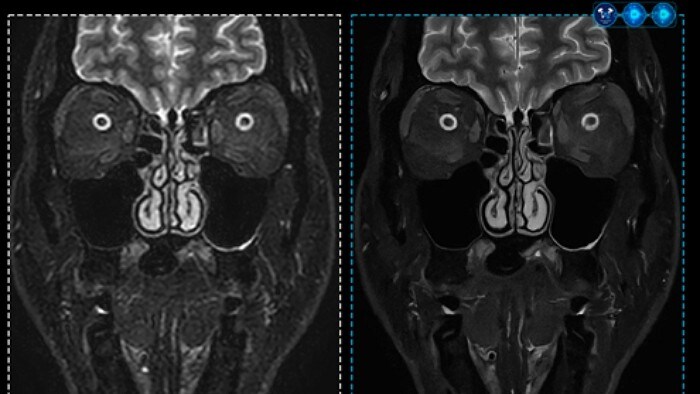

이번에 처음 소개된 ‘어드밴스드 비주얼라이제이션 워크스페이스(Advanced Visualization Workspace)’ [4] 는 필립스의 서버형 영상 데이터 분석 솔루션인 인텔리스페이스포털(IntelliSpace Portal, ISP)의 워크플로우 장점을 그대로 유지하며 AI 알고리즘을 이용한 분석 기능을 지원해 더욱 신속하고 정확한 영상 분석을 돕는다. 특히, 허혈성 뇌졸중 환자를 평가하는 AI 기반의 ASPECT(Alberta Stroke Program Early CT Score) 기능이 탑재돼 뇌졸중 환자의 조기 진단에 기여한다.

AI 기반의 새로운 CT 장비인 인사이시브 CT5100 (CT5100-Incisive System) [7] 도 선보였다. 이 솔루션은 갠트리 제어 시스템을 향상하고 환자 테이블을 확대하는 등 CT 검사 환경과 운영 효율을 개선하기 위한 CT 스마트 워크플로우 (CT Smart Workflow) 설계가 적용됐다. 또한, 인공 신경망을 이용한 딥러닝 기반 AI를 접목해 촬영 부위 및 장기별 특성에 맞게 CT 이미지를 재구성할 수 있는 기법인 프리사이즈 이미지(Precise Image) 기술이 탑재됐다. 이를 통해 저선량 촬영 시 발생하는 노이즈와 왜곡을 크게 줄여 고화질 영상을 제공한다.